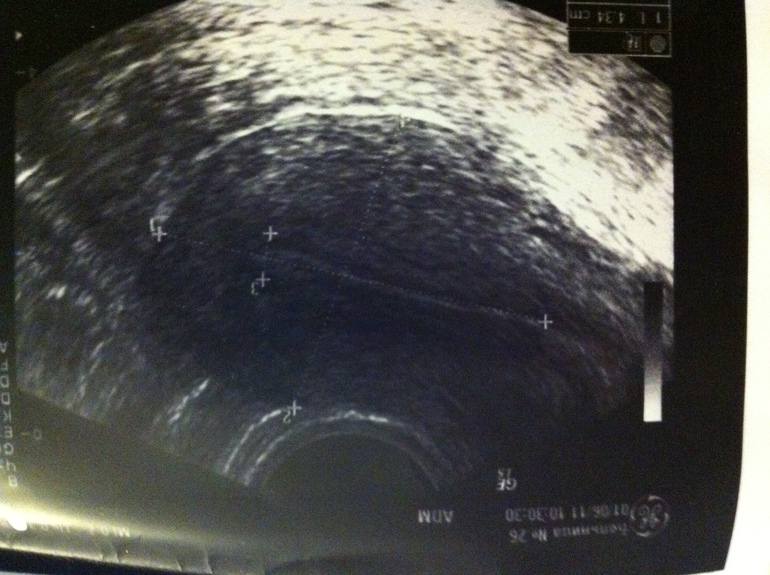

два разных УЗИ, это матка, обычно там крестики и черточки, о которых я говорила)

на фото обычно есть крестики...ими отмечают длину, ширину и т.д. посмотрите, просто качество фото не очень и я не вижу.